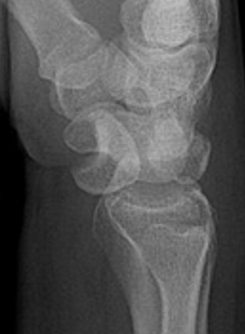

Gilula carpal arcs

Normally there are 3 smooth carpal arcs on PA xray

Arc I: Proximal cortical margins of proximal carpal row Arc II: Distal carpal margin of the proximal carpal row Arc III: Proximal cortices of the capitate and hamate |

Disruption of Gilula's 3 smooth carpal arcs / triangular lunate

Normal versus disruputed Gilula's carpal arcs

Piece of pie / triangular appearance of lunate